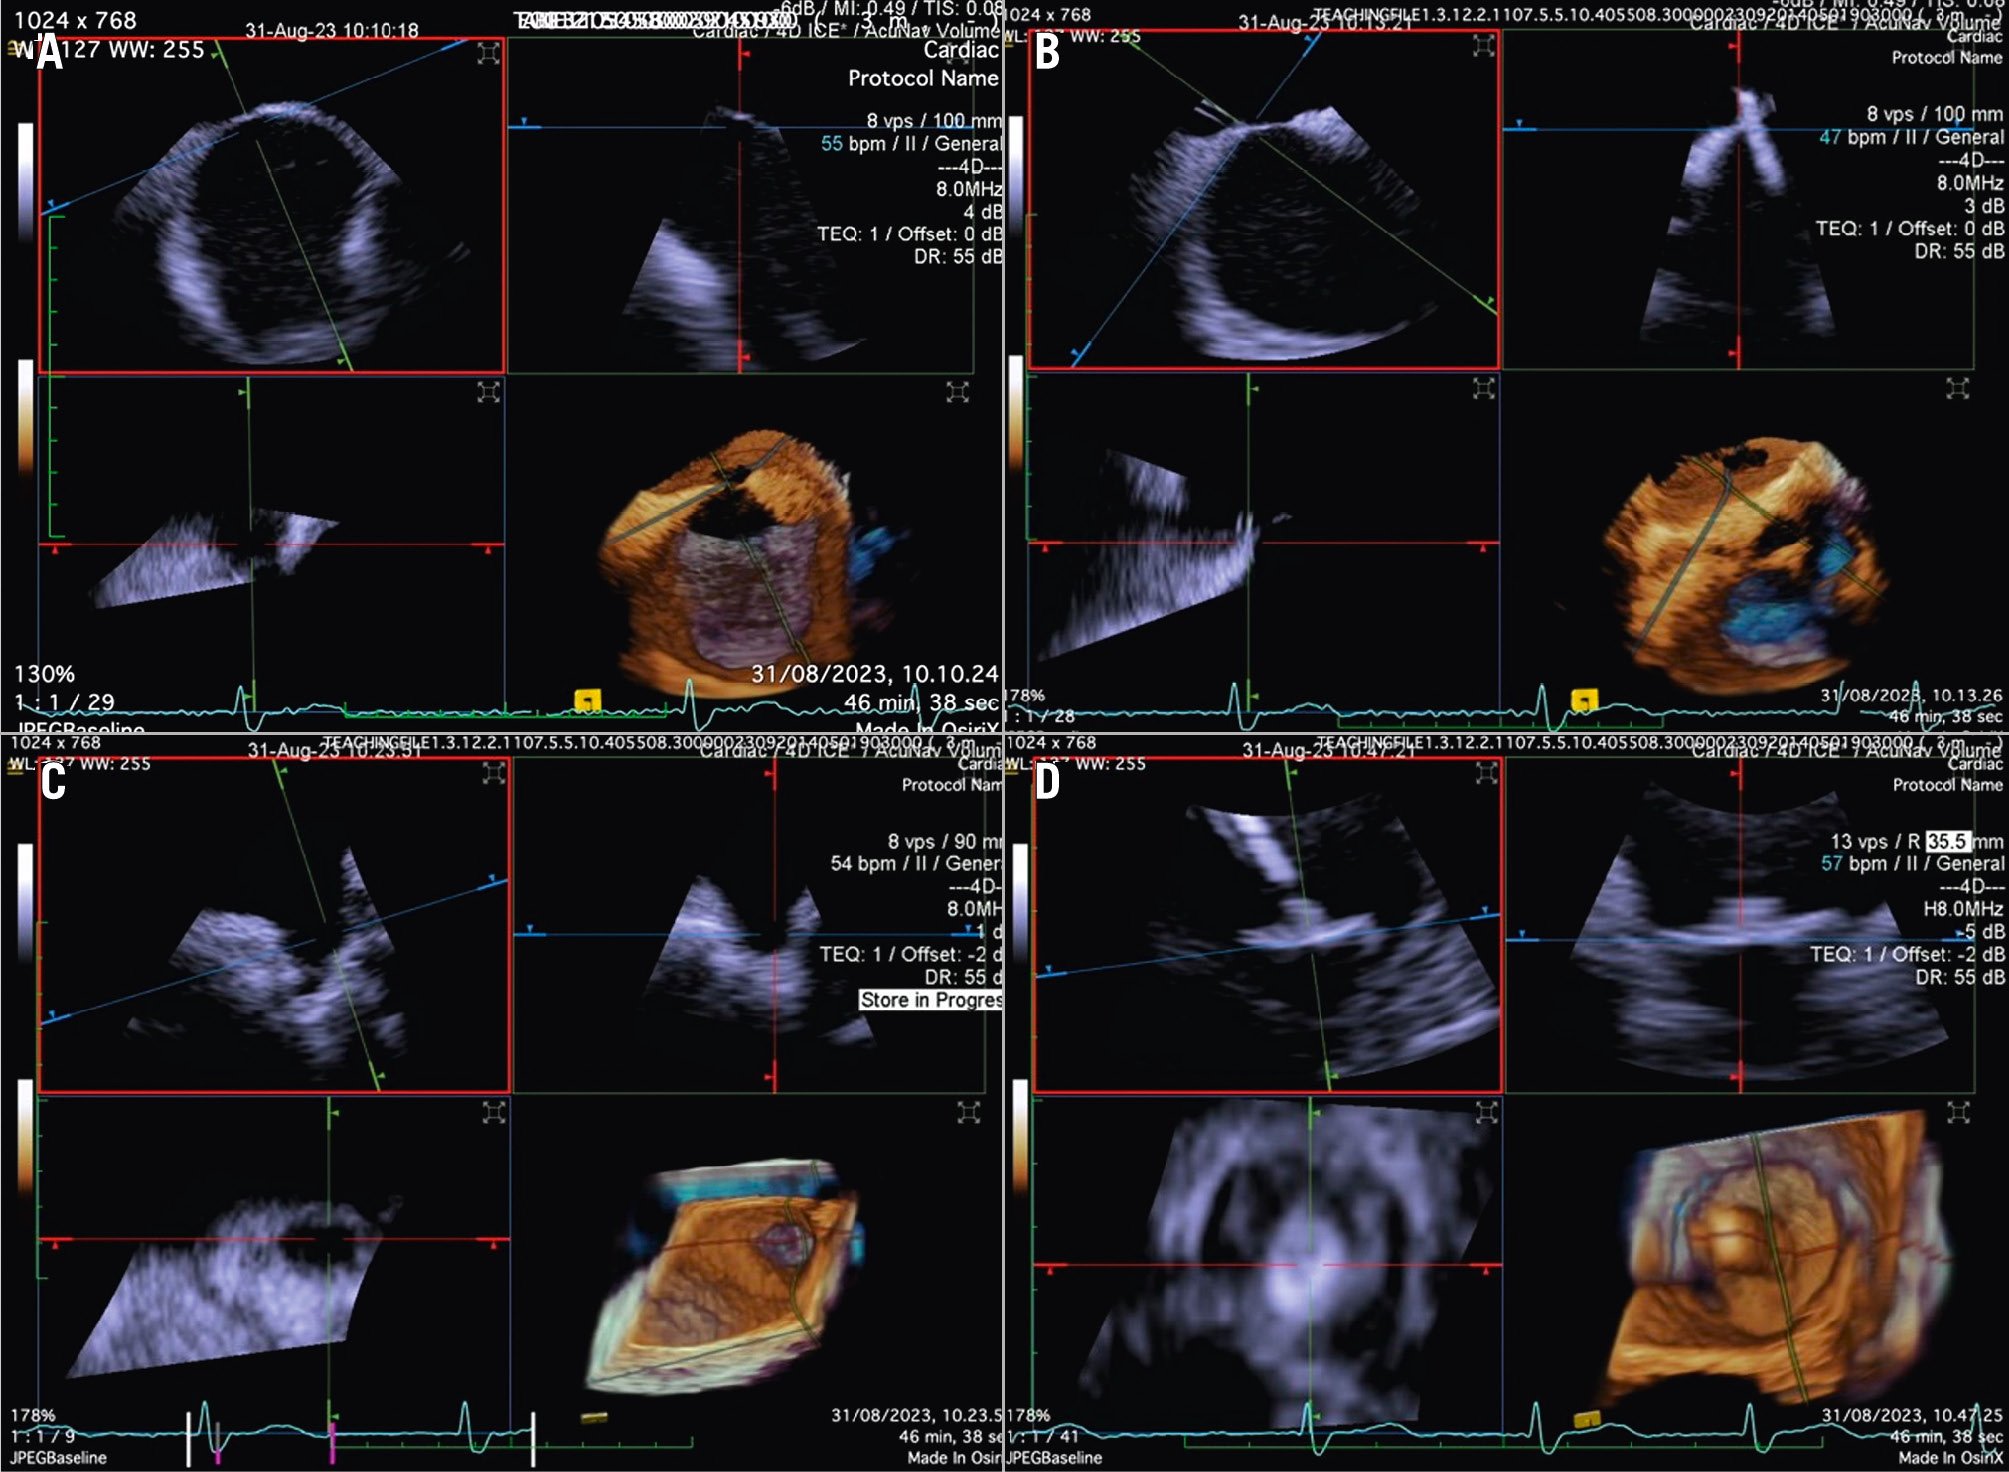

In the majority of LAAO procedures, inferior and posterior transseptal punctures are needed to obtain coaxial alignment between the delivery system and the LAA central axis. When using 3D ICE, the probe is initially best positioned in the middle of the left atrium with a frontal view of the LAA. In comparison to the use of 2D ICE, 3D ICE enables reliable measurements of the LAA dimensions at a chosen depth by using the MPR function (Figure 10). Once the measurements have been taken, the ICE catheter can be placed in the left upper pulmonary vein, with a good view of the LAA structures and the left circumflex artery. After the LAA occluder is deployed, ICE can be used to check its positioning, anchoring, size/device compression, and sealing. All of these items can be checked with 3D ICE using fewer positions than with 2D ICE (Figure 11, Moving image 14-Moving image 15-Moving image 16-Moving image 17).

PFO/ASD closure

Although PFO/ASD procedures can be performed using a simple 2D ICE probe, in some more challenging anatomical settings (e.g., floppy interatrial septum [IAS], doubt about PFO/small ASD, particular PFO tunnel), 3D ICE can be of added value. When 3D ICE is used for PFO or ASD procedures, positioning within the right atrium is sufficient. With 3D ICE, the septal defect can be visualised in a 3D volume and typically only a catheter position is needed. When starting the procedure, the operator should screen patients for additional septal defects that may have been missed on the preprocedural imaging and determine whether there is a floppy interatrial septum (for PFO) and a sufficient superior and inferior rim (for ASD). Three-dimensional ICE allows us to determine the size of the septal defect (especially for an ASD closure), guide occluder deployment, verify placement post-deployment, and screen for residual shunts1 (Figure 12, Figure 13, Moving image 18-Moving image 19-Moving image 20-Moving image 21-Moving image 22).